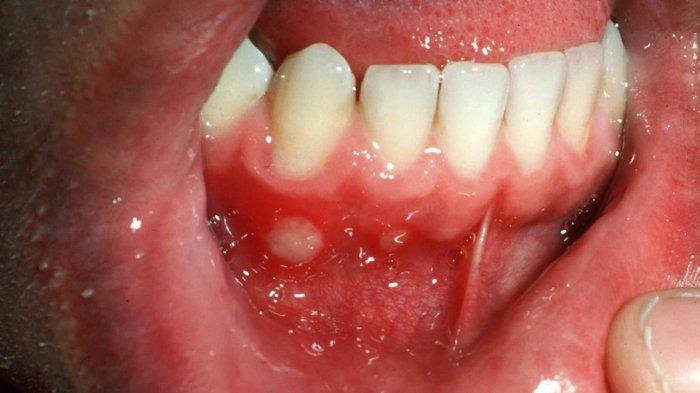

TRIBUNPONTIANAK.CO.ID- Sariawan yang ada di mulut dan gusi bisa disebabkan oleh infeksi jamur Candida Albicans.

Pengobatan sariawan sendiri bergantung pada penyebabnya. Apabila sariawan yang kamu alami disebabkan oleh infeksi, biasanya dokter akan meresepkan antibiotik, antijamur, atau obat untuk meredakan nyeri sariawan.